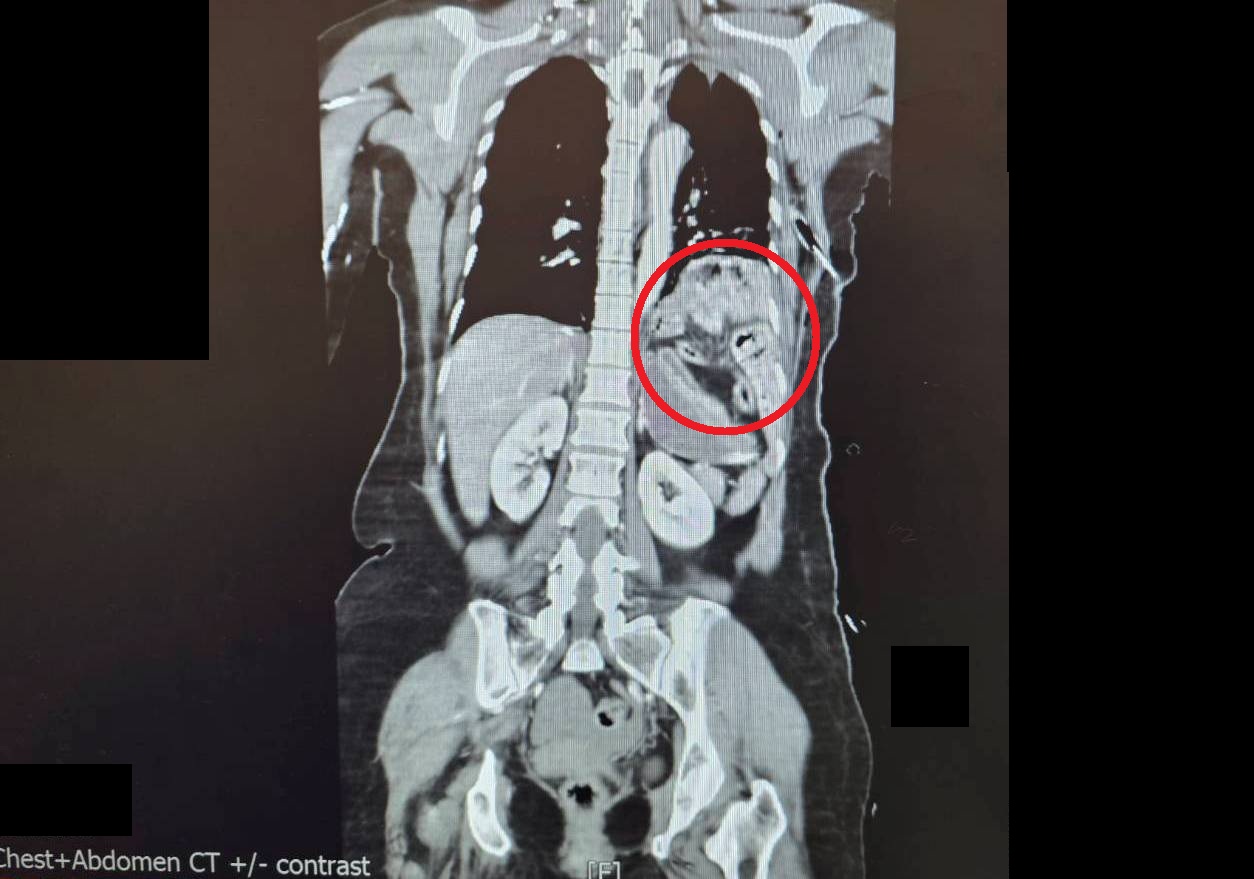

患者到院時出現雙側氣胸與皮下氣腫,呼吸困難,經電腦斷層掃描發現,左側橫隔膜破裂,原本位於腹腔的胃部與腸道被擠入左側胸腔,導致左肺無法正常擴張;同時合併下腹部大量出血(腸繫膜血管破裂)、左腳踝骨折,以及背部2至3度擦燙傷,屬於典型多重重大外傷個案。

傷者因巨大撞擊力導致外傷性橫膈疝氣,使得腸胃位移到胸腔(紅圈處)